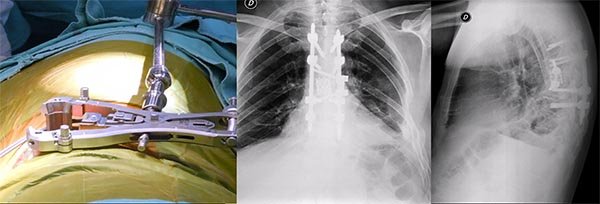

Figura 2:

Caso 24. A y B: Fractura horizontal que compromete cuerpo, pedículo izquierdo y apófisis espinosa de L1 (L1: B1; N1 AOSpine). C y D: Estabilización percutánea T12-L2.

Figura 3:

Caso 24. A: Fractura L1: B1; N1. B: Control 7 meses que evidencia consolidación. C y D: Retiro de osteosíntesis a los 9 meses con buena movilidad en las radiografías dinámicas de control.

Figura 5:

Caso 8. Se realizó una estabilización percutánea T6-T10. El paciente retornó a UTI, para estabilizar su cuadro respiratorio y hemodinámico.